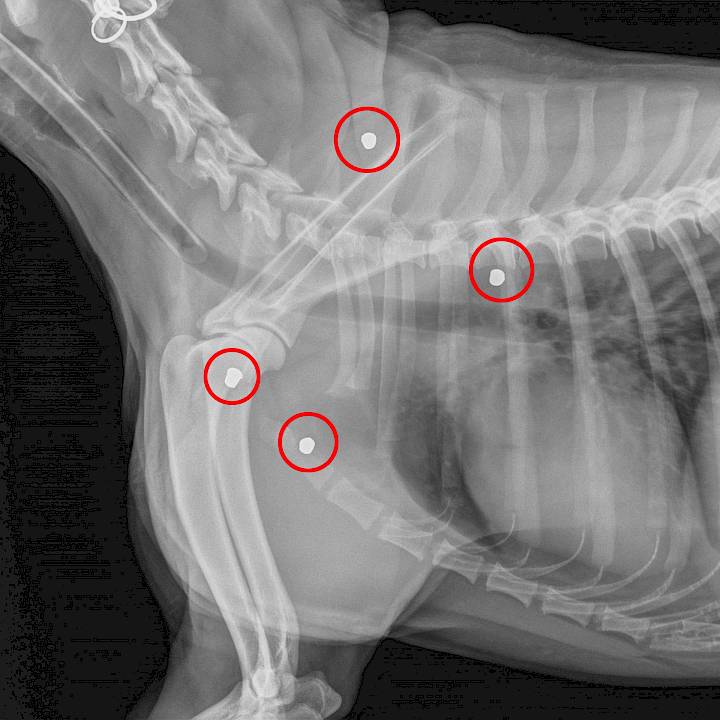

สุนัขที่ถูกยิงจนได้รับบาดเจ็บนั้นมีมากและพบได้บ่อยครั้ง เมื่อไม่นานมานี้มีสุนัขที่ถูกยิงได้รับบาดเจ็บมาพร้อมกับกระสุนที่ฝังอยู่ภายในตัวมารับการรักษาที่มูลนิธิของเรา หนึ่งในนั้นคือ สติลก้า สุนัขเพศผู้อายุประมาณ 2 ปีที่อาศัยอยู่ในชุมชนแห่งหนึ่ง เขามีลูกกระสุนปืนฝังอยู่ภายในร่างกายบริเวณหัวไหล่ซ้าย การเอ็กซเรย์ทำให้มองเห็นลูกกระสุนที่ฝังอยู่ภายใน หมอของเราได้ทำการผ่าตัดกระสุนนั้นออกไปเป็นที่เรียบร้อยแล้ว และสุนัขก็ปลอดภัยแล้วแต่ยังคงต้องพักฟื้นอยู่กับเราอีกสักระยะหนึ่ง

พิซซ่า คือสุนัขอีกตัวหนึ่งที่ถูกยิงมาเช่นกัน แต่โชคร้ายที่พิซซ่าไม่สามารถรอดจากการบาดเจ็บได้เนื่องจากกระสุนฝังเข้าในบริเวณที่สำคัญ